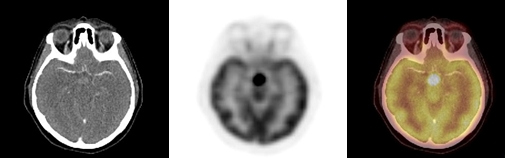

Se obtuvo un estudio PET-CT de cuerpo entero 50 minutos después de la administración IV de 7,8 mCi de 18F-FDG; el componente CT se realizó con medio de contraste yodado (equipo Siemens mCT). El estudio demostró lesiones osteolíticas hipermetabólicas en la cabeza humeral derecha, cavidad glenoidea y partes blandas adyacentes con valor de captación estandarizado (SUVmax) = 9,2. También mostró múltiples lesiones osteolíticas e hipermetabólicas vertebrales y costales con masa de partes blandas hipermetabólica que infiltra la musculatura dorso-lumbar y femoral. Se observó aumento del metabolismo en el plano cutáneo de axila izquierda y vulva, en correspondencia con lesiones ulceradas, así como también un nódulo hipofisario de 14 mm, hipermetabólico, con SUVmax = 22,5 (figs. 1,2 y 3 A). Los pulmones, mediastino, hígado, bazo, glándulas suprarrenales y páncreas no presentaron alteraciones del metabolismo ni tampoco se identificaron adenopatías hipercaptantes.

Un 18FDG PET-CT de control post-terapia (figs. 1,2 y3 B) mostró significativa disminución metabólica de la lesión hipofisaria, del componente de partes blandas en hombro derecho y de las lesiones en columna, con persistencia sin cambios de las lesiones osteolíticas en TAC. Dada la respuesta parcial a la terapia, se inicia segundo curso de vinblastina semanal 6 mg/m2 por 6 semanas y prednisona 40 mg/m2 por 3 días a la semana.